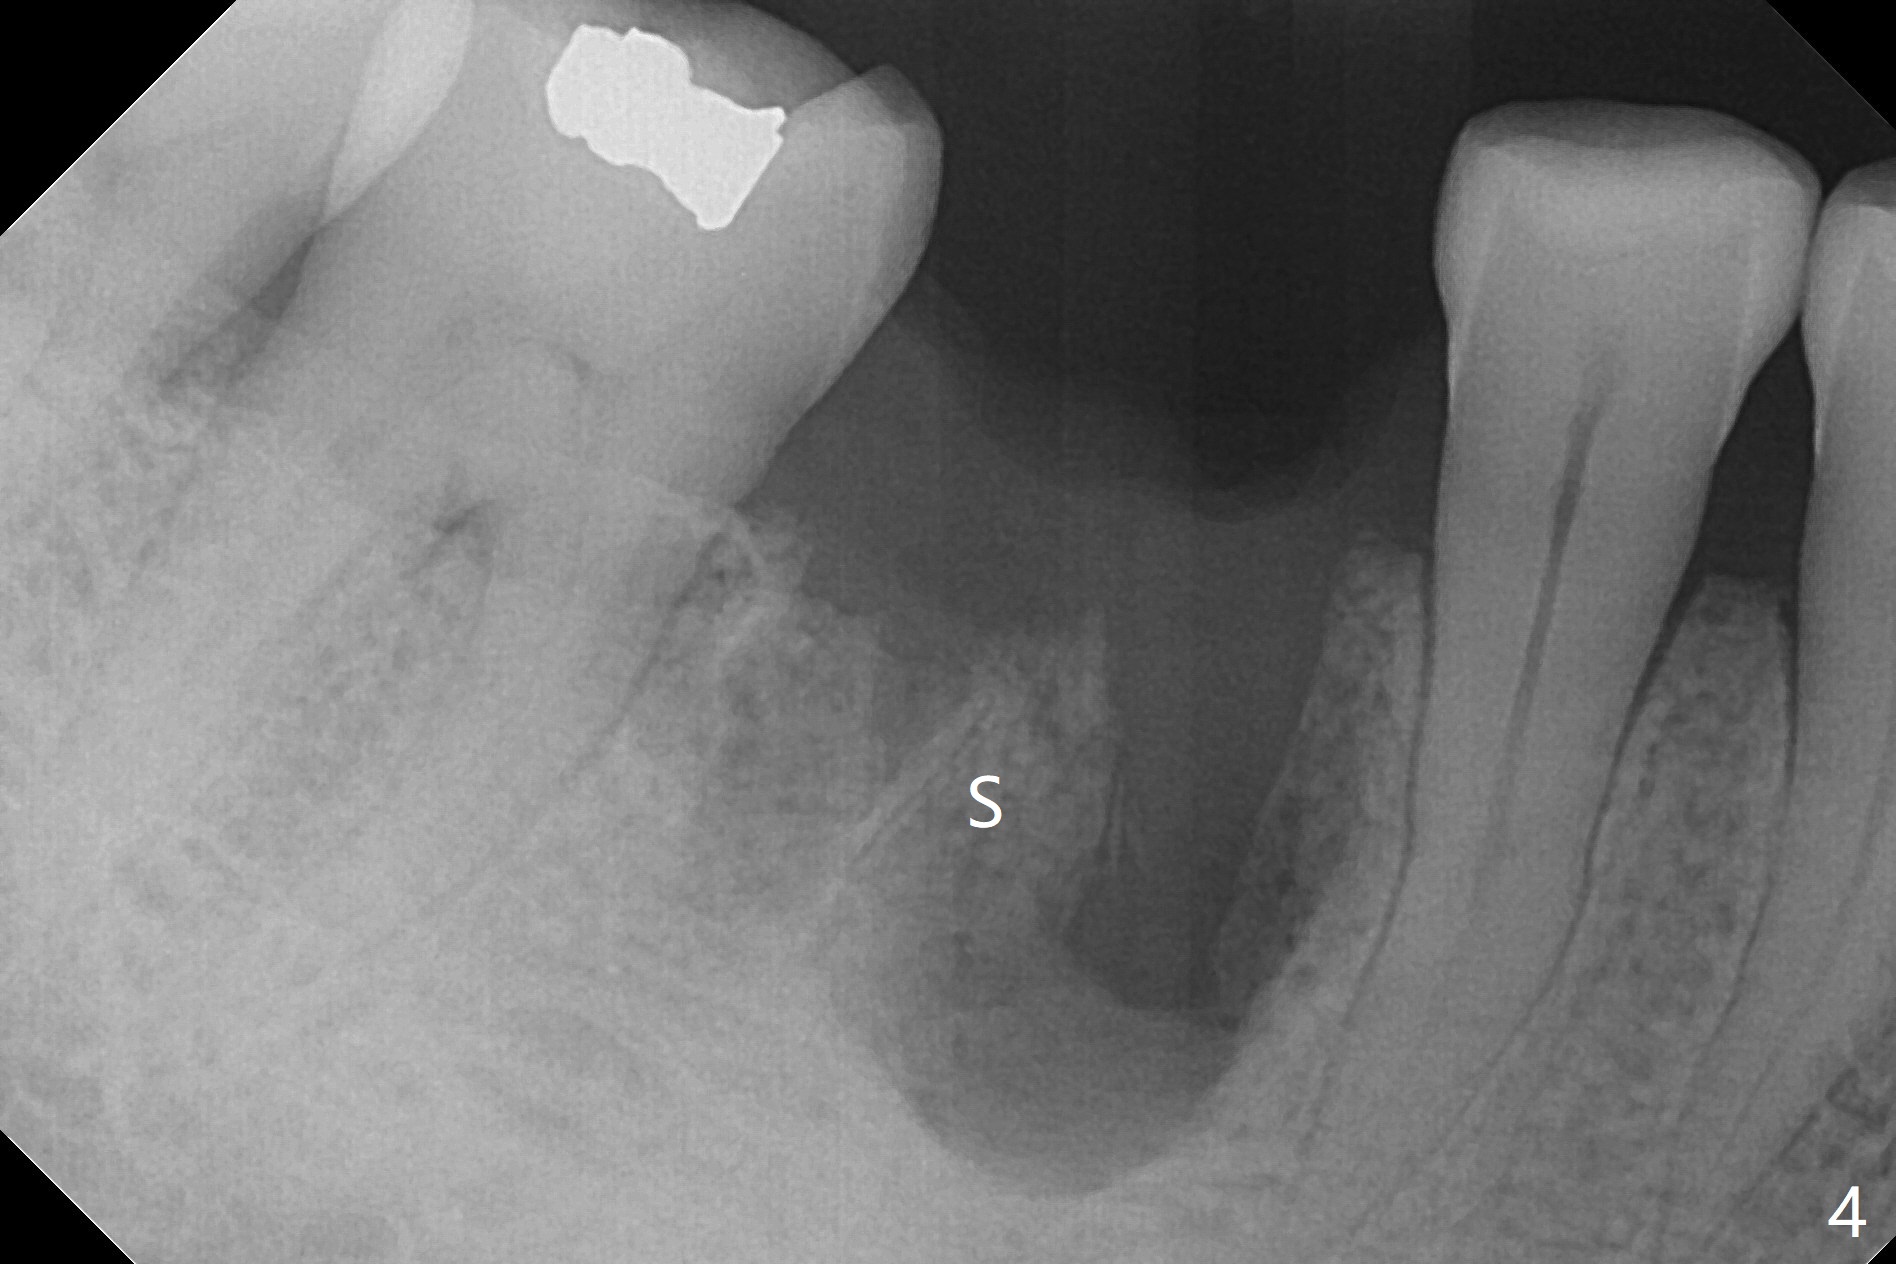

Preop oral Amoxicillin seems to be associated with reduction in the buccal and lingual (Fig.3 arrow) fistulae at #30, but there is mesiobuccal swelling (Fig.1 *) with 7 mm pocket (Fig.2). Osteotomy is initiated in the middle of the septum (Fig.3-5 S). As the osteotomy increases, it shifts mesially (Fig.6 arrow). Guided surgery is able to reduce shifting. A 5x13 mm implant is not seated completely (Fig.7) apparently due to osteotomy shifting. After removal of the bone from the osteotomy distally, the implant remains unseated with lower torque value (Fig.8). Following reuse of the 4.3 mm drill deeper by 1-2 mm, the implant is seated to a satisfactory depth (Fig.9 with increase in torque to 50 Ncm) with placement of Vera Graft (*) and a 7.5x4(3) mm abutment. After a second round of allograft placement (Fig.10 *), the implant is found to be 4 mm from the IAC. At the later stage of osteotomy, the coronal end of the septum is destroyed with loss of osteotomy depth landmark. It is apparent that the soft tissue landmark may be more reliable. The implant threads appear to be covered by the bone graft 3.5 months postop (Fig.11). The abutment is changed to 6.5x5(3) mm one before impression with minor margin prep. The bone density seems to increase 5 months postop, i.e., immediately post cementation (Fig.12) and 10 months postop (5 months post cementation (after retightening abutment), Fig.13 (*)). Periimplantitis develops mesiobuccally, consistent with bone loss 1 year 7 months post cementation (Fig.14 *); the implant seems to have been buccally placed. Bone graft is necessary with PRF or GEM21S if the vein is small and 6-month membrane with a hole around a 7.5x4(4) cemented abutment for easy wound closure. Take 5x5 CM CBCT to determine which wall has defect, buccal or lingual. Check mesial contact. If so, remove the crown, reseat the abutment (possible incomplete seating) and re-impress after bone graft.